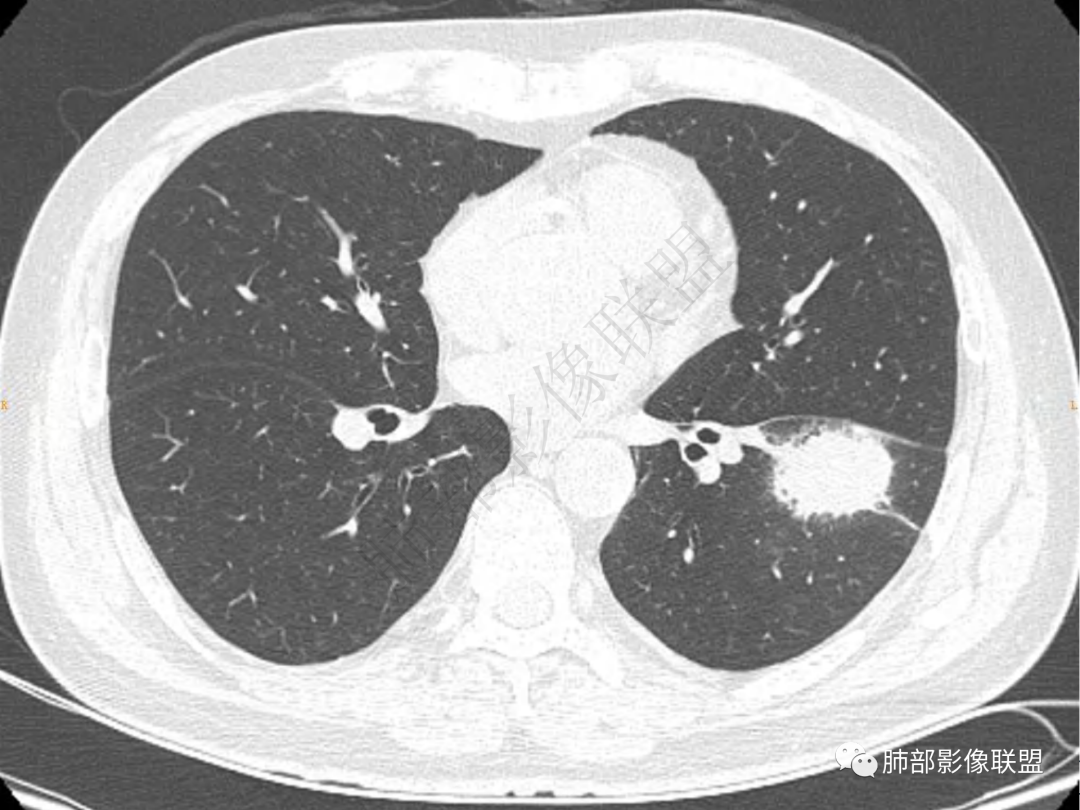

4.实性部分不均匀环形强化并显示一小范围低密度坏死区或空洞。较之肺窗,整体纵隔窗范围较小,提示病灶并不十分密实。抑或为不同时段图像。

肺脓肿:可宽基底与胸膜相连,附近胸膜增厚——炎性特点

二、形态、边缘:

肺脓肿:边界模糊不清,或者块影为类圆形,无明显分叶,边缘平直为主,刀切征——炎性特点三、病灶周围特点:肺脓肿:病灶非远端有片状GGO——炎性特点四、近端支气管阻塞:肺脓肿:常有引流支气管伴管壁增厚或者支气管沿洞壁走行。五:坏死壁:肺脓肿:大多壁厚,少数壁薄,没有壁结节,内壁清楚光整——炎性特点

六:增强扫描:

肺脓肿:环形强化,强化较显著。如出现明显囊壁样强化甚至边缘“憩室”样突出,高度支持肺脓肿。